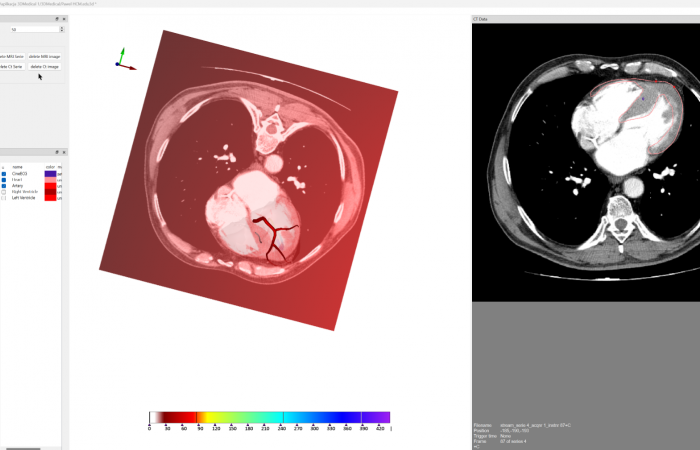

Pracownia Funkcjonalnego i Wirtualnego Medycznego Obrazowania 3D (Pracownia 3D-FM) funkcjonuje w strukturze Zakładu Diagnostyki Obrazowej Szpitala Uniwersyteckiego w Krakowie pod kierownictwem Prof. dr hab. Tadeusza Popieli. Jej celem jest opracowanie i wdrożenie innowacyjnych metod przetwarzania oraz analizy sygnałów i obrazów medycznych, w tym wykorzystanie technologii rzeczywistości wirtualnej oraz metod obrazowania funkcjonalnego. Rozwiązania te wspierają przedoperacyjne planowanie, monitorowanie procedur medycznych oraz wzbogacają proces diagnostyczny o nowe formy wizualizacji danych medycznych.

Zakres działalności

Pracownia 3D-FM zajmuje się m.in. następującymi obszarami:

- Tworzeniem modeli 3D do celów przedoperacyjnego planowania oraz wizualizacji diagnostycznej.

- Rozwojem rozwiązań programowych do obrazowania medycznego.

- Obrazowanie Medyczne 3D

- Segmentacja i analiza danych DICOM

- Rekonstrukcja danych medycznych

- Obrazowanie funkcjonalne

- Elektrokardiograficzne obrazowanie 3D (ECGI)

- Modelowanie fizjologiczne

- Analiza sygnałów czasowych, w tym EKG

Pracownia Funkcjonalnego i Wirtualnego Medycznego Obrazowania 3D łączy nowoczesne technologie z praktycznym zastosowaniem w diagnostyce i terapii. Dzięki interdyscyplinarnej współpracy oraz zaawansowanym narzędziom badawczym dążymy do podnoszenia standardów opieki medycznej w Szpitalu Uniwersyteckim w Krakowie.